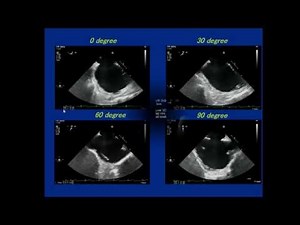

3D-TEE imaging for ASD closure

12,6mii vizualizări

22 mai 2015

YouTube

APCIS

Types of ASD echocardiography

11,7mii vizualizări

26 iul. 2023

Pediatric Echo Gallery